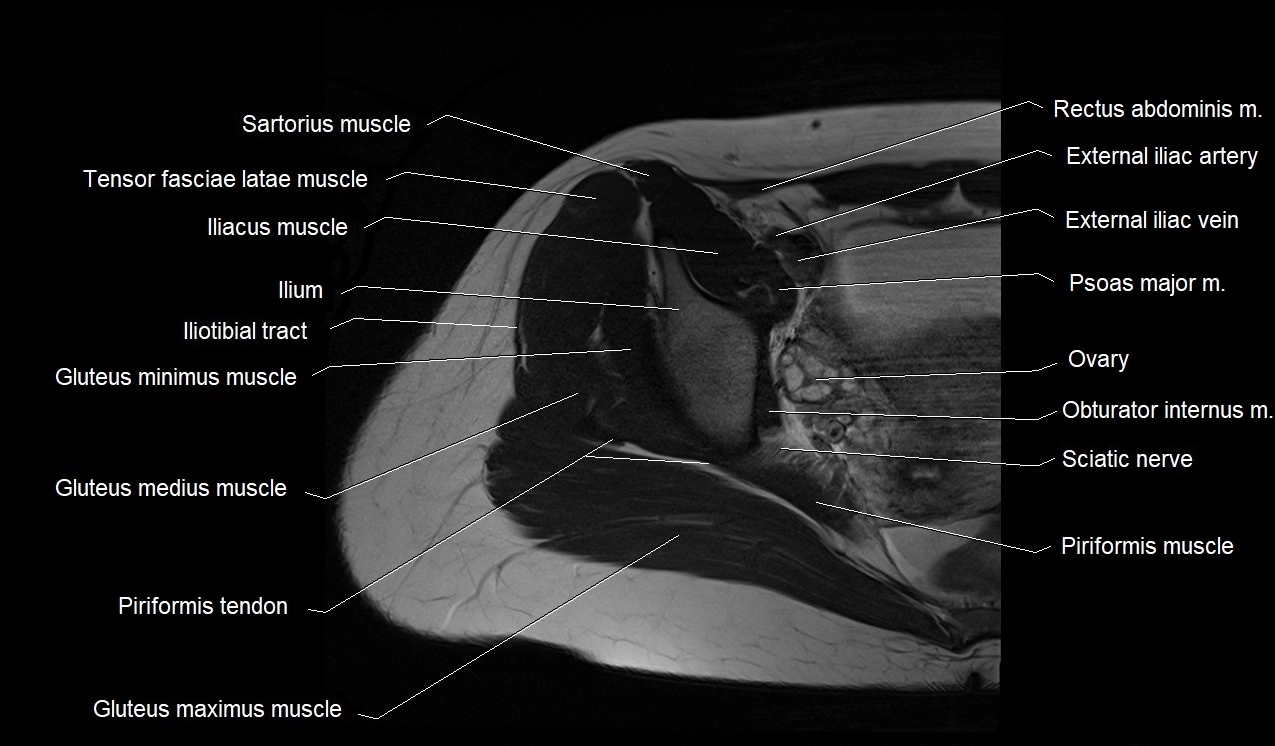

- Gluteus maximus muscle

- Gluteus medius muscle

- Gluteus minimus muscle

- Iliotibial tract

- Obturator internus muscle

- Quadratus femoris muscle

- Sartorius muscle

- Tensor fasciae latae muscle